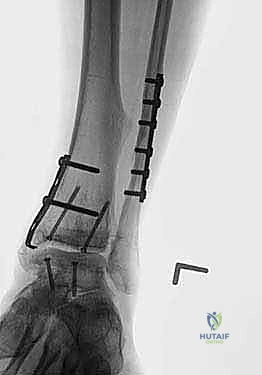

- Fluoroscopic Confirmation of Apposition and Anatomy:

<a href="/media/hutaif_opertive/hutaif-ch67-total-ankle-she-p4058-0bb

Additional Intraoperative Imaging & Surgical Steps